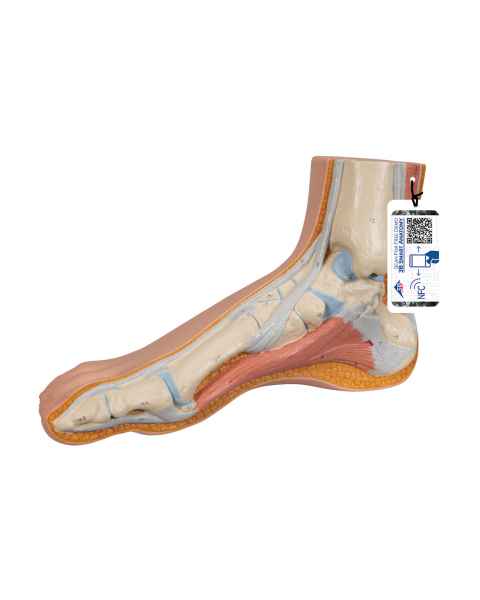

Extremity Models

While the majority of vital human organs are located inside of the head and torso, human appendages are just as important in terms of day-to-day functionality. In order to depict the parts and workings of these limbs, doctors and teachers rely upon extremity anatomical models.

With the assistance of extremity anatomy models, patients and students have a tangible tool to better understand their appendages, as well as potential injuries that are afflicting them or require treatment. Our extensive selection of extremity models includes arm anatomical models, foot models, hand anatomy models, and leg models.